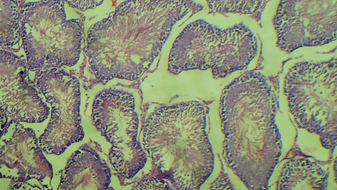

Comparative Analysis of Gastrointestinal Motility in Lead, Cadmium, and Mercury Exposed Wistar Rats

Microbiome Modulatory Role of Fermented Sphenostylis Stenocarpa and Fermented Coccus Nucifera in Mitigating Effect of Colitis Ulceration in Experimental Rats

Effect of Hydro Ethanolic Seed Extract of Datura Metel on the Histology and Biochemistry of Liver Tissue of Sprague Dawley Rats